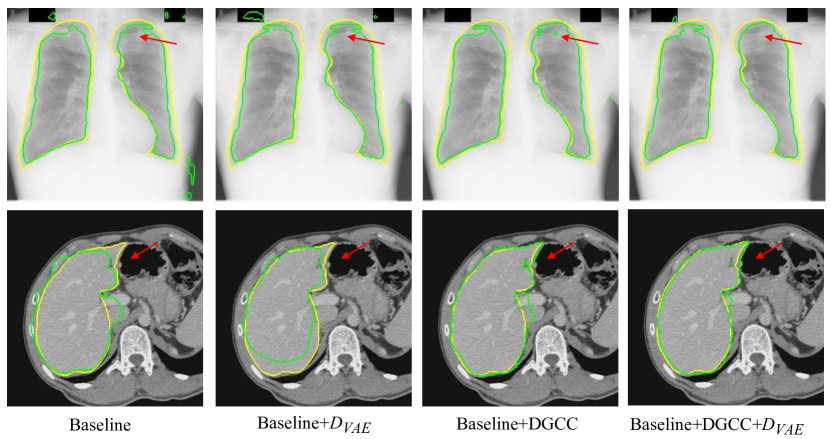

We first evaluate the effectiveness of our pseudo label generation method. For an ablation study of our , we started with the baseline of training a CycleGAN [30] without and DGCC. Table 2 shows quantitative evaluation results of the output of on the validation set with different latent vector length of the VAE. It can be observed that the best performance is achieved when the length of latent vector is 32. Fig 5 shows that the optimal value of hyper-parameter is 1.0, and the performance of does not change much when is around 1.0. We also compared our with three counterparts: 1) the baseline not using , 2) our without , 3) replacing the VAE with beta-VAE [62] where the latent vector length was 32, denoted as (beta). Quantitative evaluation based on the testing set in Table 1 shows that our outperformed the counterparts, and compared with not using , it improved the average Dice from 0.909 to 0.918 for optic disc segmentation and from 0.904 to 0.918 for fetal head segmentation, respectively. Fig. 3 demonstrates the effectiveness of our VAE-based discriminator on the output of .

We further evaluated the effectiveness of our multi-scale DGCC module by ablation studies. We compared it with two variants: 1) DGCC(l) that only calibrates the low-resolution feature map obtained by the bottleneck of ; 2) DGCC(h) that only calibrates the high-resolution feature map before the last convolution block of . The quantitative evaluation results of these variants combined with our baseline model are shown in Table 3. It can be observed that our multi-scale DGCC has a higher performance than DGCC(l) and DGCC(h), which demonstrates that multi-scale calibration performed better than single-scale calibration of the pseudo label generator . We also compared the calibrated result at of our DGCC with the result at (i.e., before calibration) of our DGCC module, which is denoted as DGCC(). The quantitative results in Table 3 and qualitative results in Fig. 4 show that the calibration helps to reduce and even remove some noise in the output of . In addition, Fig. 3 and Table 3 show that combining our with DGCC outperforms the other variants.

We first evaluate the effectiveness of our pseudo label generation method. For ablation studies, we started with a baseline of training a CycleGAN [30] without and DGCC. It was compared with baseline+, baseline+ without , baseline+DGCC, and baseline++DGCC. Table 5 lists quantitative evaluation results of the output of for our testing set. It shows that our improved the average Dice score from 0.823 to 0.839 for lung segmentation and 0.853 to 0.869 for liver segmentation compared with the baseline. Using and DGCC at the same time outperformed the other variants, with an average Dice score of 0.848 for lung segmentation and 0.889 for liver segmentation. Fig. 12 shows a visual comparison between these variants. It can be observed that the output of trained by the baseline method contains some noise. By using that introduces a high-level shape constraint, the noise is reduced. DGCC also helps to improve the quality of ’s output compared with the baseline. The last column of Fig. 12 shows that a combination of and DGCC obtained better results than the others.